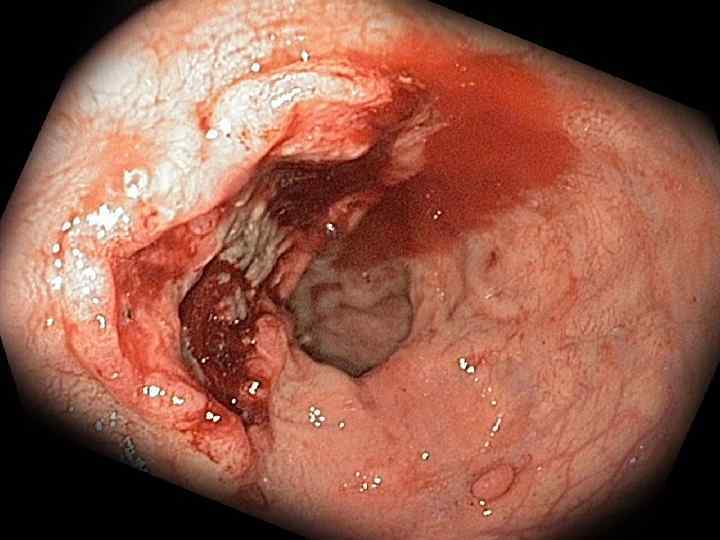

Перфорация язвы желудка и ДПК Анамнез Наличие язвы в анамнезе — у 80 90% больных; «немые» язвы — у 10 15% больных; наличие продромальных симптомов (боль, тошнота, рвота). Характерно острое начало с боли в животе, напряжение мышц брюшной стенки. Начальная реакция организма на перфорацию язвы схожа с патогенезом шока, что связано с ожогом брюшины кислым желудочным соком, излившимся в брюшную полость. В последующем развивается серозно фибринозный, а затем гнойный перитонит.

Клиническая картина Характерна резкая боль в эпигастральной области. Сначала локализуется в верхних отделах живота, при прободении язвы 12 перстной кишки – больше справа от срединной линии, затем по всей правой половине живота, захватывая правую подвздошную область, и далее – по всему животу. Возможна иррадиация болей в плечи и правую лопатку. Может быть рвота «кофейной гущей» или, редко, ярко алой кровью. Характерно исчезновение печеночной тупости из за наличия свободного газа в брюшной полости.

Клиническая картина Основные симптомы: Симптом Спижарного — исчезновение печеночной тупости при перкуссии; Симптом Де Кервена пальцевидное втяжение рентгеновской тени желудка по большой кривизне, обусловленное рефлекторным спазмом циркулярных мышц желудка при язве малой кривизны.

Клиническая картина Основные симптомы: Симптом Щеткина Блюмберга — усиление боли при резком снятии пальпирующей руки от брюшной стенки; Симптом Воскресенского (симптом «рубашки» ) — ощущение усиления боли в правой подвздошной области при быстром проведении правой ладонью по передней брюшной стенке правого подреберья вниз по натянутой левой рукой хирурга рубашке больного.